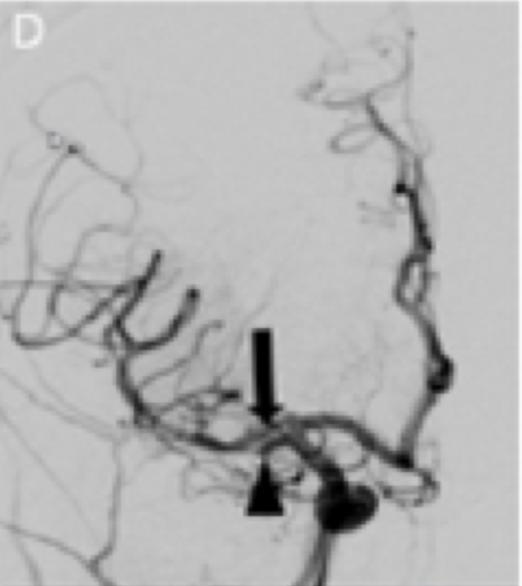

微导管/微导丝组件通过ACE60导管从右侧大脑前动脉(ACA)A1段进入AMCA的一支。ACE60导管从微导管/微导丝组件上向前推进,直至血栓处。借助ACE60导管和负压抽吸泵进行血栓抽吸术。单次通过后,自右侧ACA-A1段发出的AMCA分支实现了再通(图1D)。

虽然ACE60和ACE68的远端内径(ID)受到影响(分别为0.060英寸和0.068英寸),但这确保了最佳的吸入力和较少的导管穿行过程中血管损伤的机会。由于起源于大脑前动脉的一支大脑中动脉会形成豆纹动脉(图1C),因此首先处理该支大脑中动脉,随后处理另一支。